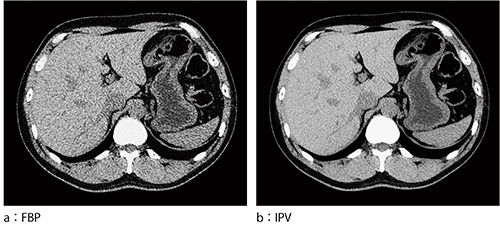

Supria Opticaは,AI技術を活用して設計された画像再構成技術である“IPV”*2を搭載した。IPVは,心臓撮影が可能な64列CT装置である「SCENARIA View」に実装されている技術であり,これをSupria Opticaにも実装した。IPVは十分な反復処理により得られる画像を教師データとして,高精度の処理を高速化することを可能とした。IPVは独自のビジョンモデル技術を開発し,rawデータを起点とした画像再構成処理をすることにより,noise power spectrum(NPS)をfiltered back projection(FBP)に近づけ,違和感のない質感を実現した。また,低コントラスト検出能は最大2倍に改善する。図2に,IPV適用画像例を示す。被ばく低減と視認性の両立に関した画像例で,IPVの適用により被ばく量が83%低減している。

図2 IPV処理例(被ばく低減と視認性)*3

*3 「IPV」の項で掲載している臨床画像(図2)は,SCENARIA Viewで撮影した画像である。